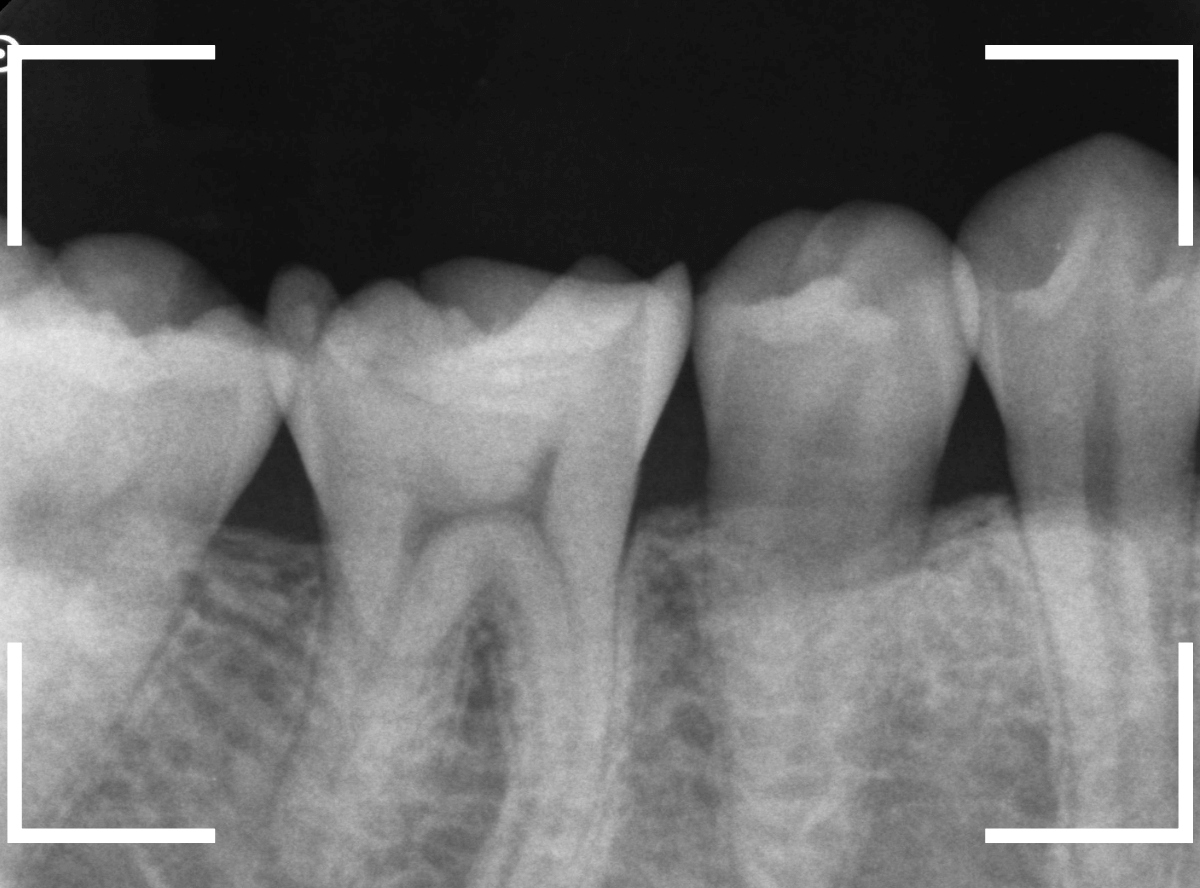

レントゲン写真で確認します。

赤い線がレジンが入っている部分。

青い線が歯の神経です。

かなり神経の近いところまでレジンがつめてあるのがわかりますが、虫歯が側面からどの程度進んでいるのかはよくわかりません。

レントゲン写真だけみると、治療の必要がなさそうにも見えます。

このように、初見では虫歯になっている事が明らかなのに、レントゲン写真ではまったくわからないとう事もあります。